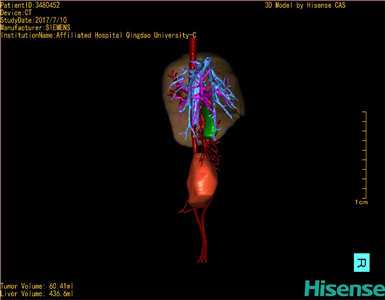

通过调节窗宽窗位调整CT序号,对肿瘤,肝实质,胆囊,下腔静脉,肿瘤,肝动脉、门静脉及肝静脉等进行三维重建;系统自动计算肿瘤体积和肝脏体积。模拟手术操作,自动计算切除肿瘤体积。肝脏体积为436.6ml,肿瘤体积为60.41ml,与血管联系紧密,术前手术方案的规划。

术前三维重建:

重建图片